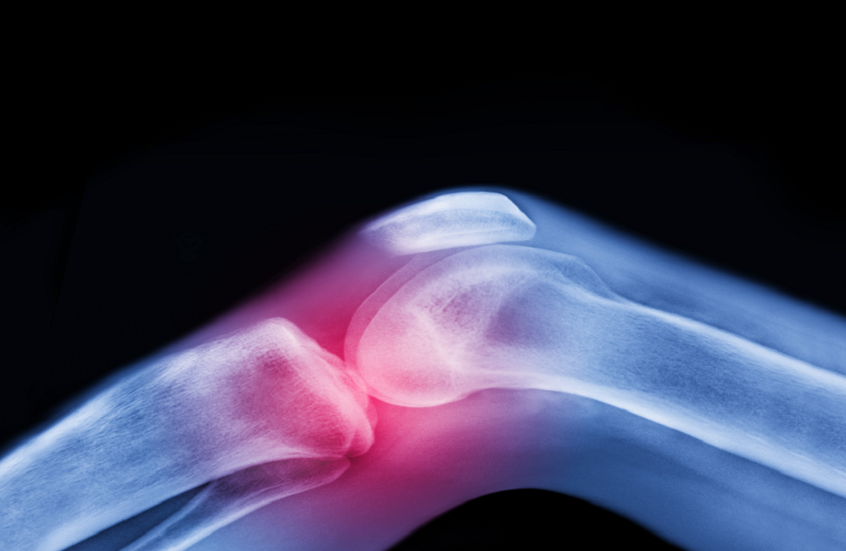

ابتكار ثوري .. ركبة بشرية حية قد تنهي معاناة آلام المفاصل

ابتكر علماء طريقة جديدة لعلاج التهاب المفاصل التنكسي (الفصال العظمي) عبر زراعة ركبة بشرية حية في المختبر، في خطوة قد تغير حياة الملايين من المرضى.

ويهدف هذا الإنجاز إلى استعادة وظيفة المفصل الطبيعية وتخفيف الألم الذي يعيق الحركة اليومية.